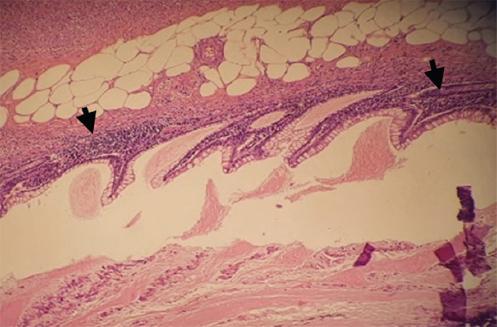

Exploratory laparotomy was performed, finding cone-shaped surgical mesh eroding the parietal peritoneum, with adhesions to the omentum, cecum, and cecal appendix (Fig. 2). A 10x1 cm erythematous, edematous, and hyperemic cecal appendix, with the presence of appendicolith at the tip. Finally, an appendectomy was performed by dismantling the surgical mesh cone and closure of the peritoneum. The mesh was placed using the Lichtenstein technique in its entirety. The patient evolved favorably and was discharged 24 h after surgery. Pathology revealed cecal appendix with reactive lymphatic hyperplasia and passive congestion (Figs. 3-5).

Figure 2 Surgical mesh (black arrow) eroding parietal peritoneum (green arrow), cecal appendix (red arrow), and mesoappendix (blue arrow).